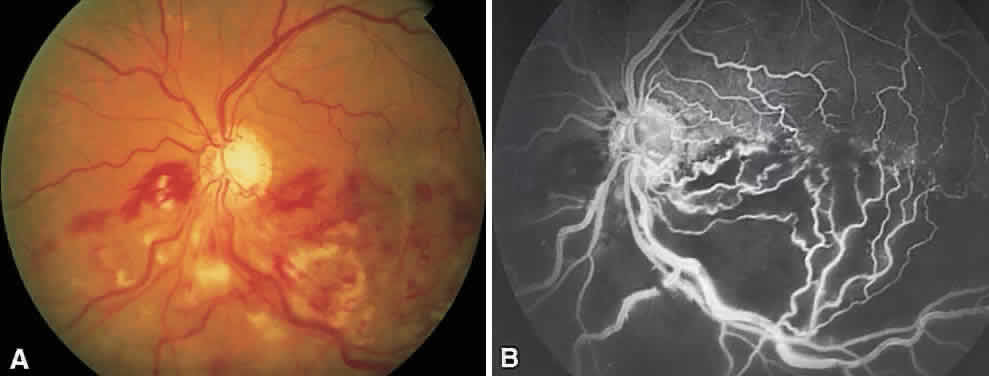

In the DRS, certain high-risk characteristics (HRCs) were identified as being the most accurate prognostic indicators of visual loss. HRCs include neovascularization on or within one disc diameter of the disc (NVD) that is equal to or greater than one fourth to one third of the disc area in extent or any NVD or retinal neovascularization else-where (NVE) associated with preretinal or vitreoushemorrhage (Fig. 1B). For eyes with these clinicalcharacteristics, prompt PRP is recommended. Forpatients with severe or severe nonproliferativediabetic retinopathy (NPDR), as well as for patientsin whom adequate follow-up cannot be ensured, early scatter therapy may be considered.26 The presence of rubeosis iridis or neovascular glaucoma in the setting of PDR, even without HRCs, may warrant PRP.27–29